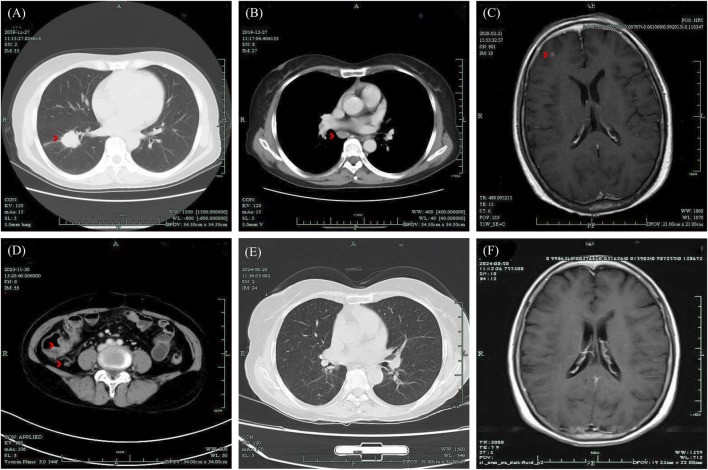

Case presentation: We report the case of a 62-year-old woman with NSCLC and brain metastases, who tested positive for ALK. She had been treated with Alectinib for nearly 4 years. The patient experienced diarrhea for 4 days, and a subsequent colonoscopy revealed pancolitis along with multiple ulcers in the terminal ileum and ileocecal valve. Given the severity of these symptoms, classified as a grade 3 adverse event by the Common Terminology Criteria for Adverse Events (CTCAE), Alectinib was discontinued. Treatment with oral enteric-coated Mesalazine tablets led to a resolution of the diarrhea and a significant improvement in the pancolitis and ulcers upon follow-up. The patient's anticancer therapy was subsequently switched to Ceritinib capsules. At follow-up, she demonstrated a stable tumor condition with no recurrence of intestinal ulcers or colitis.